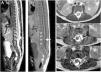

Estudio de RM de columna dorsolumbar. Secuencias sagitales TSE T2 (A) y SE T1 (B) y axiales TSE T2 (C-E). Los cortes sagitales muestran un cono medular descendido que se sitúa a nivel del cuerpo vertebral de L4 (flechas A y B) y muestra alteración de su normal morfología. En la secuencia T1 no se aprecia ningún tipo de lipoma intradural asociado. En los cortes axiales identificamos las dos hemimédulas (flechas cortas en C y D) así como la existencia de un tabique fibroóseo con un trayecto oblicuo (flechas largas en D y E), delimitando dos sacos durales independientes que corresponde a una diastematomielia tipo I con un filum terminal anclado.